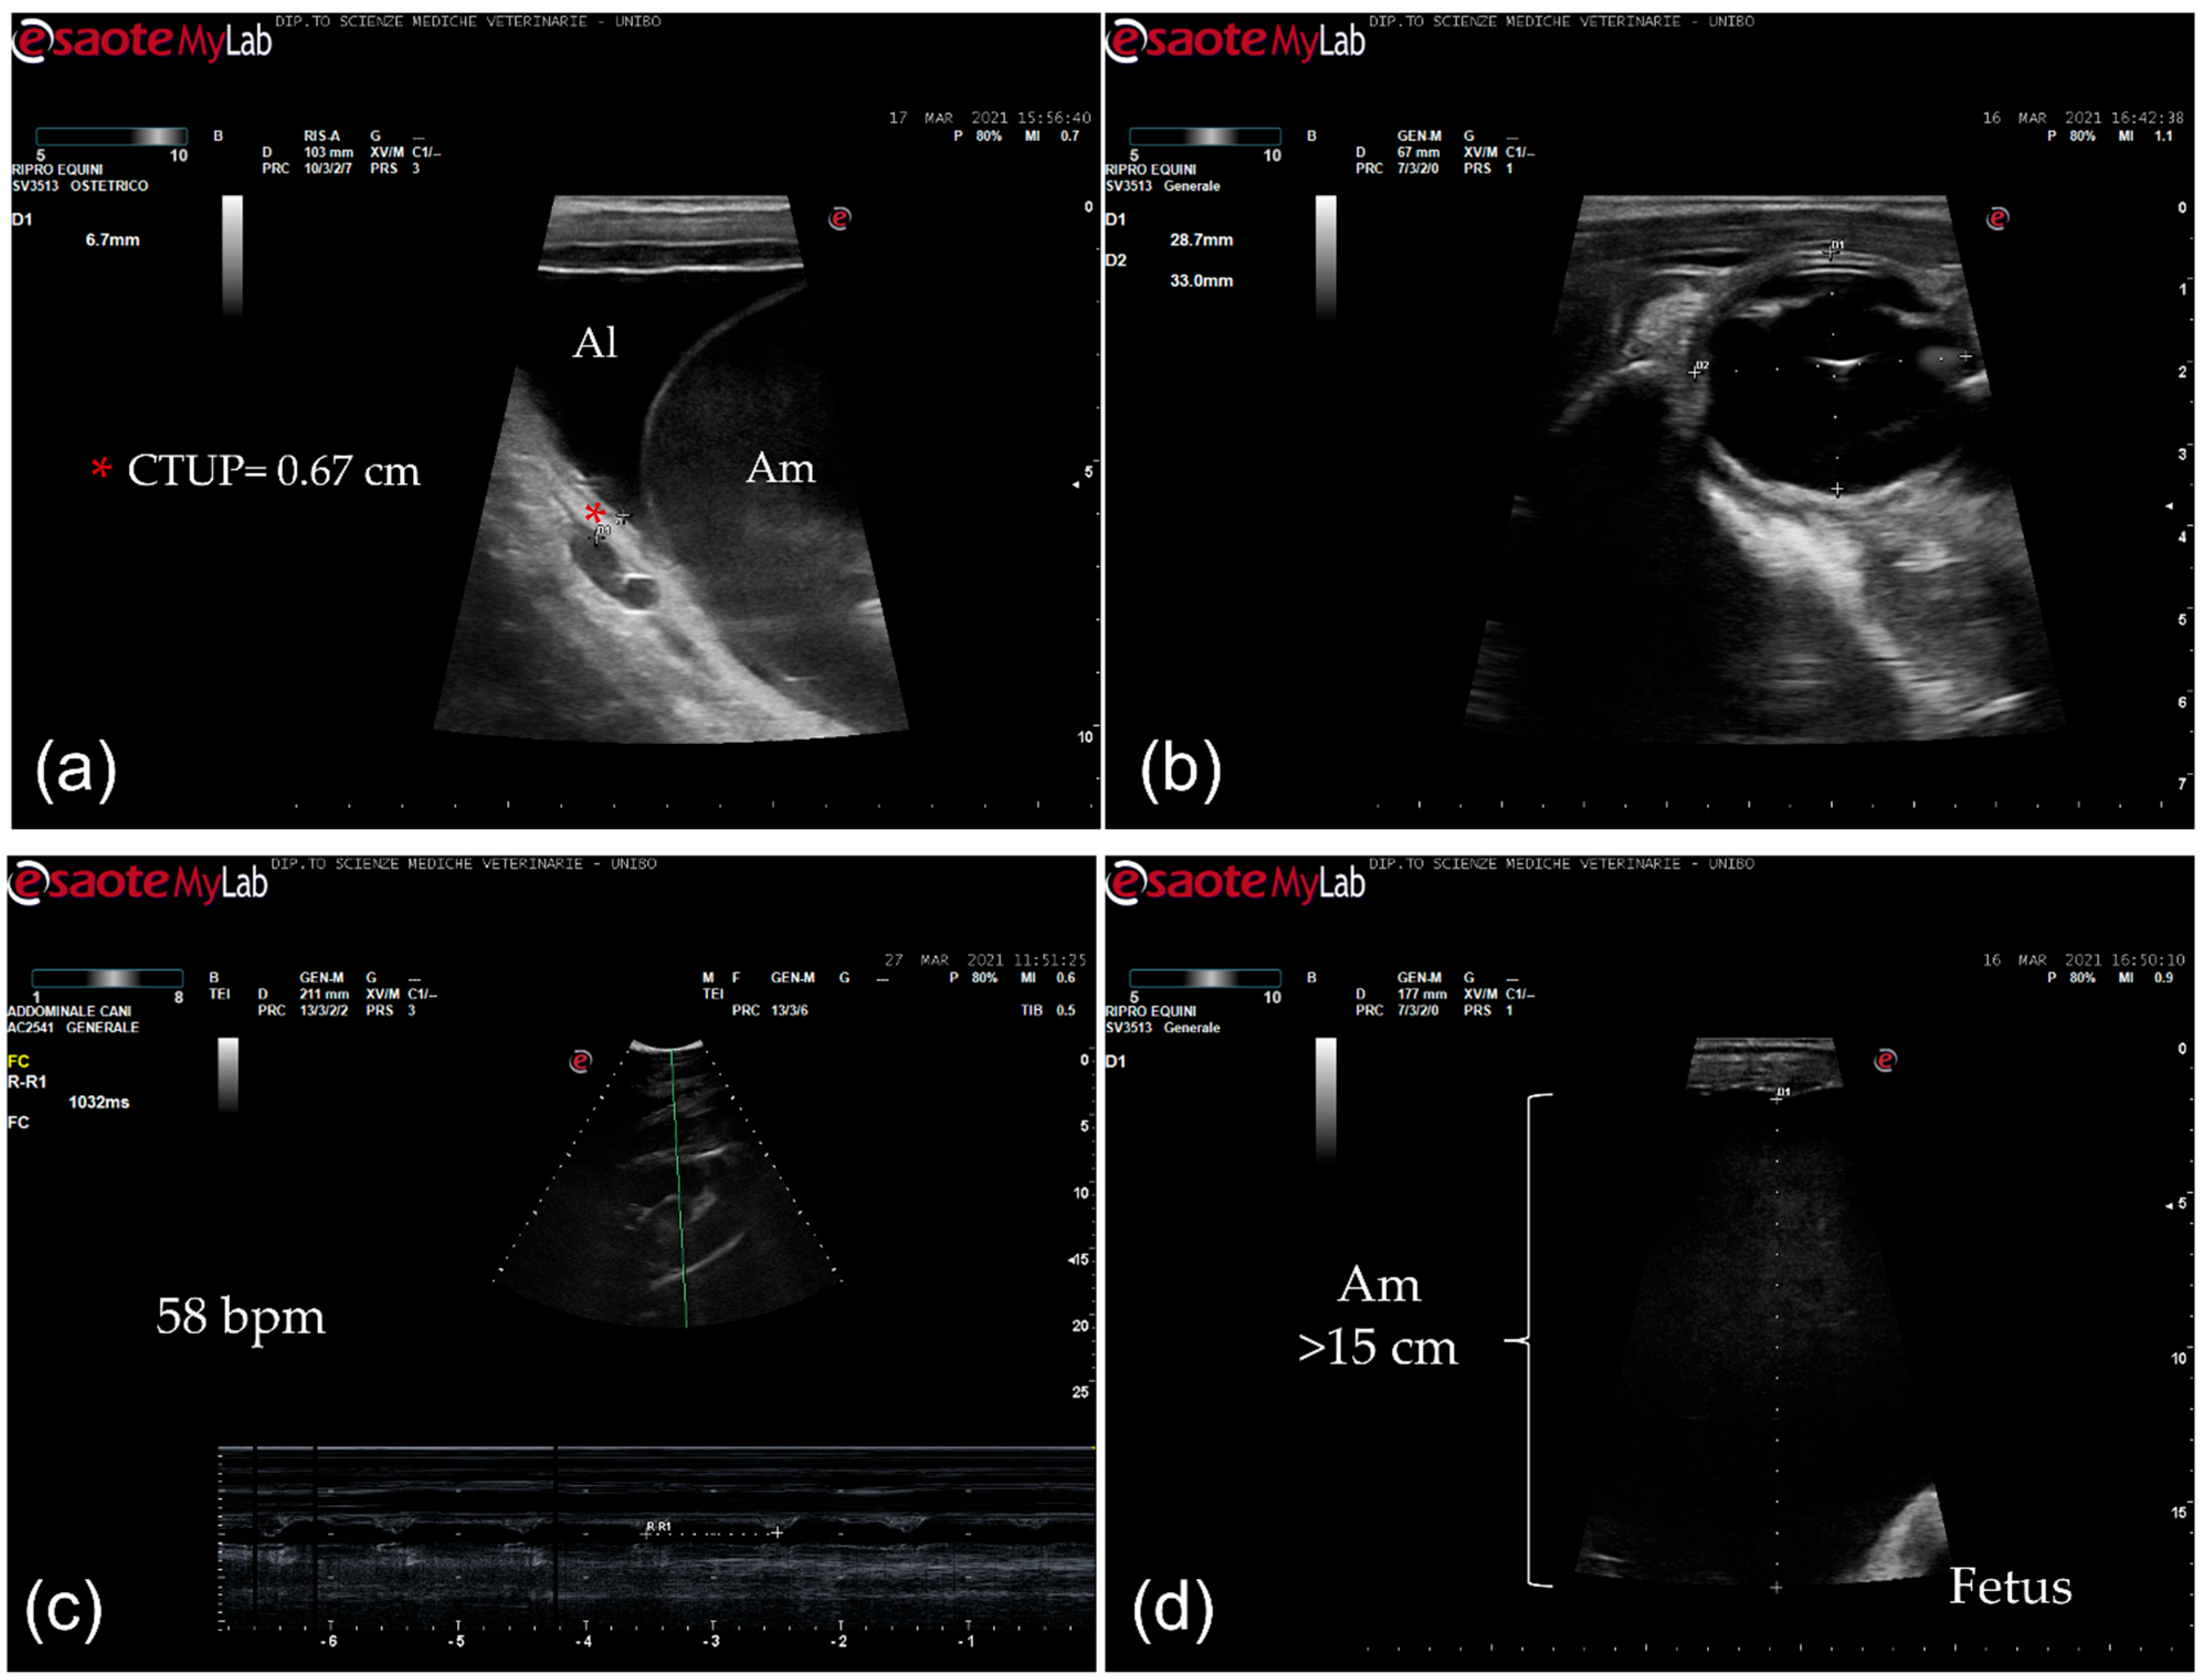

2. Clinical Description